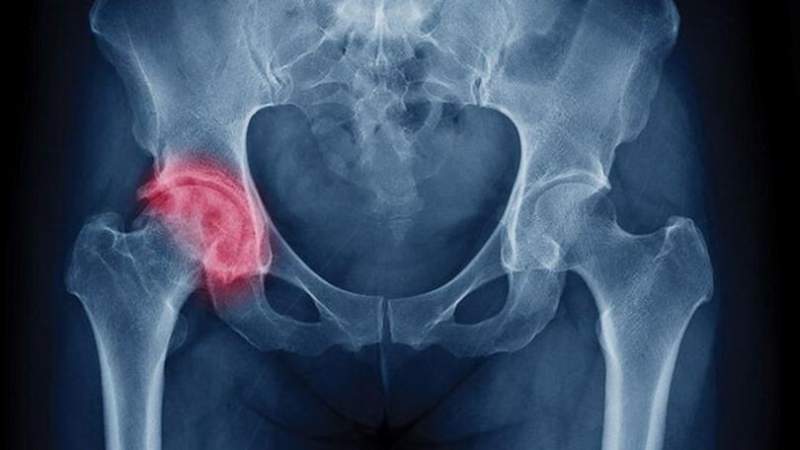

Прежде всего, любой врач должен обратить внимание на симптомы и зафиксировать реакции пациента на простые действия, упомянутые ранее. Таким образом, специалист может выдвинуть предварительный диагноз, после чего он оформляет направление на рентген, чтобы подтвердить или опровергнуть его.

Анатомия сустава довольно сложна и напоминает работу шарнира: головка кости помещена в вертлужную впадину, а капсула сустава прикреплена с одной стороны к впадине, а с другой — чуть ниже шейки.

Важно отметить, что кость окружена артериями, которые обеспечивают поступление необходимых питательных веществ к этому соединению.

При таком типе перелома происходит повреждение не только самого сустава, но и окружающих его кровеносных сосудов и нервных окончаний.